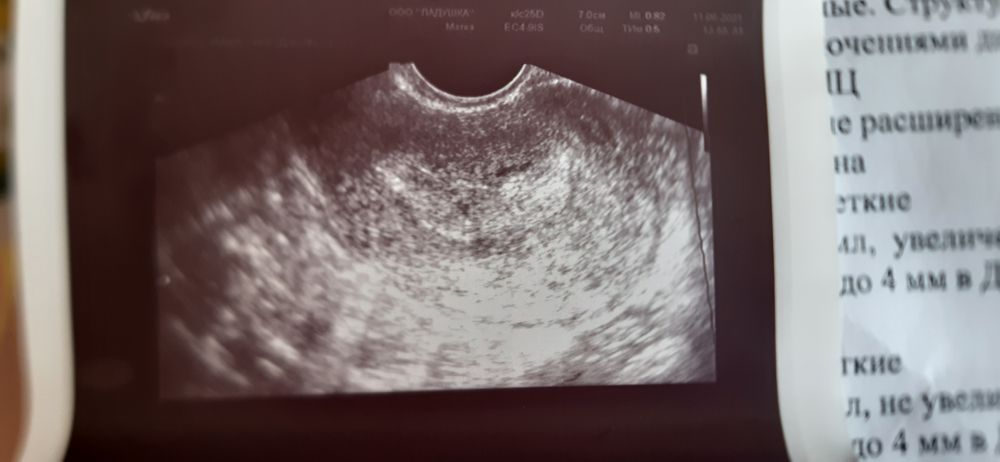

11го закровило, срок 5+2. Пошла на узи. Матка как при второй фазе, пя не увидели. Предположительно пузырный занос. 8го хгч 1193, 11го 2564( сегодня только пришел результат).

Евгения, действительно что-то странное.. ХГЧ ну совсем не похож как при пузырном заносе, если на фото полный занос, то ХГЧ ооочень низкий. Я вам уже отвечала, у меня по УЗИ ставили частичный пузырный занос.. Узист действительно нормальный? Я всех в гинекологии замучила, врачи пузырный только по книжкам знают, он 1:1000 встречается. Наверное, действительно стоит подождать, или сходить к другому.. Еще помню, что одним из признаков заноса является белок в моче.. Держитесь!!!